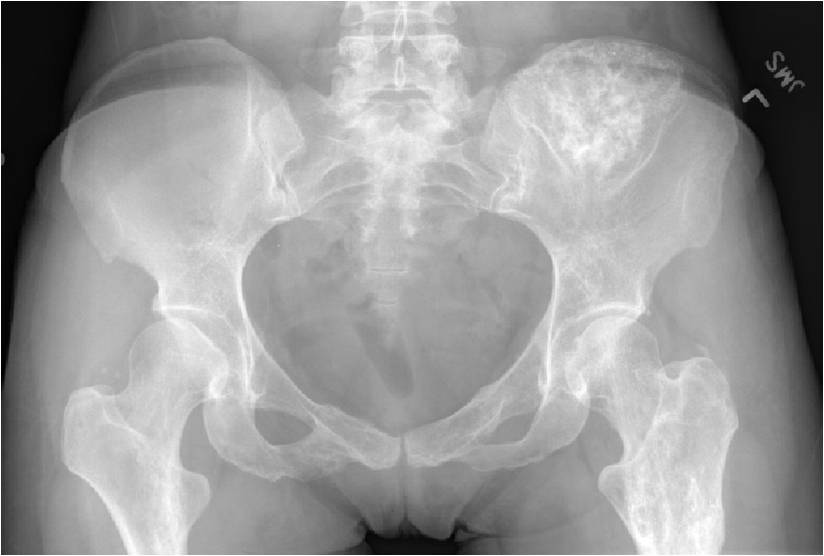

- Enchondromas of the pelvis, vertebrae and ribs are uncommon

- Almost all hyaline cartilage tumors of the pelvis are considered malignant based on anatomic location no matter what the pathology shows. These tumors will ultimately grow locally and have the potential to dedifferentiate or change into a higher grade chondrosarcoma.

Enchondromatosis

- (Multiple Enchondromas/Ollier Disease

- Enchondromatosis is a rare disorder that is not hereditary in which the patient is afflicted with multiple intraosseous cartilaginous tumors or enchondromas.

- May be predominantly unilateral or affect a single extremity/limb

- Affected limb is often shortened and deformed and angulated

- Higher risk of malignant transformation to chondrosarcoma (5-50%) as opposed to an isolated enchondroma

- Marked skeletal deformity

Enchondromas in enchondromatosis may involve the metaphysis, diaphysis, epiphysis and articular cartilage

- The most common sites to undergo malignant change are the scapula, rib cage and pelvis